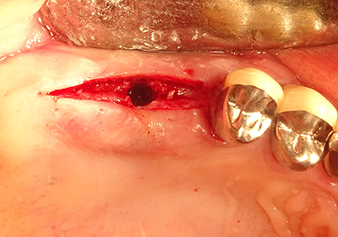

L’insert I2A (diamètre 2,0 mm) est ensuite utilisé pour perforer le plancher sinusien par intermittence et à la plus petite échelle possible. Cette méthode piézochirurgicale spéciale garantit que la membrane de Schneider n’est pas endommagée. Quand le Z25P est utilisé, la membrane est déjà légèrement relevée sous l’effet du fluide de refroidissement délivré via la pointe de l’insert (Fig. 3). Seulement 50 % du fluide de refroidissement sont éjectés afin d'éviter une pression élevée sur le site implantaire.